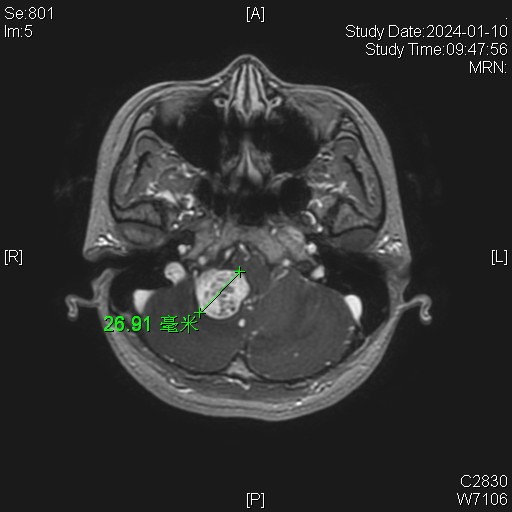

女性患者,26岁,因“间断性头晕1月余。”于2024-01-08入院。

诊断:延髓血管母细胞瘤

von Hippel-Lindau综合征